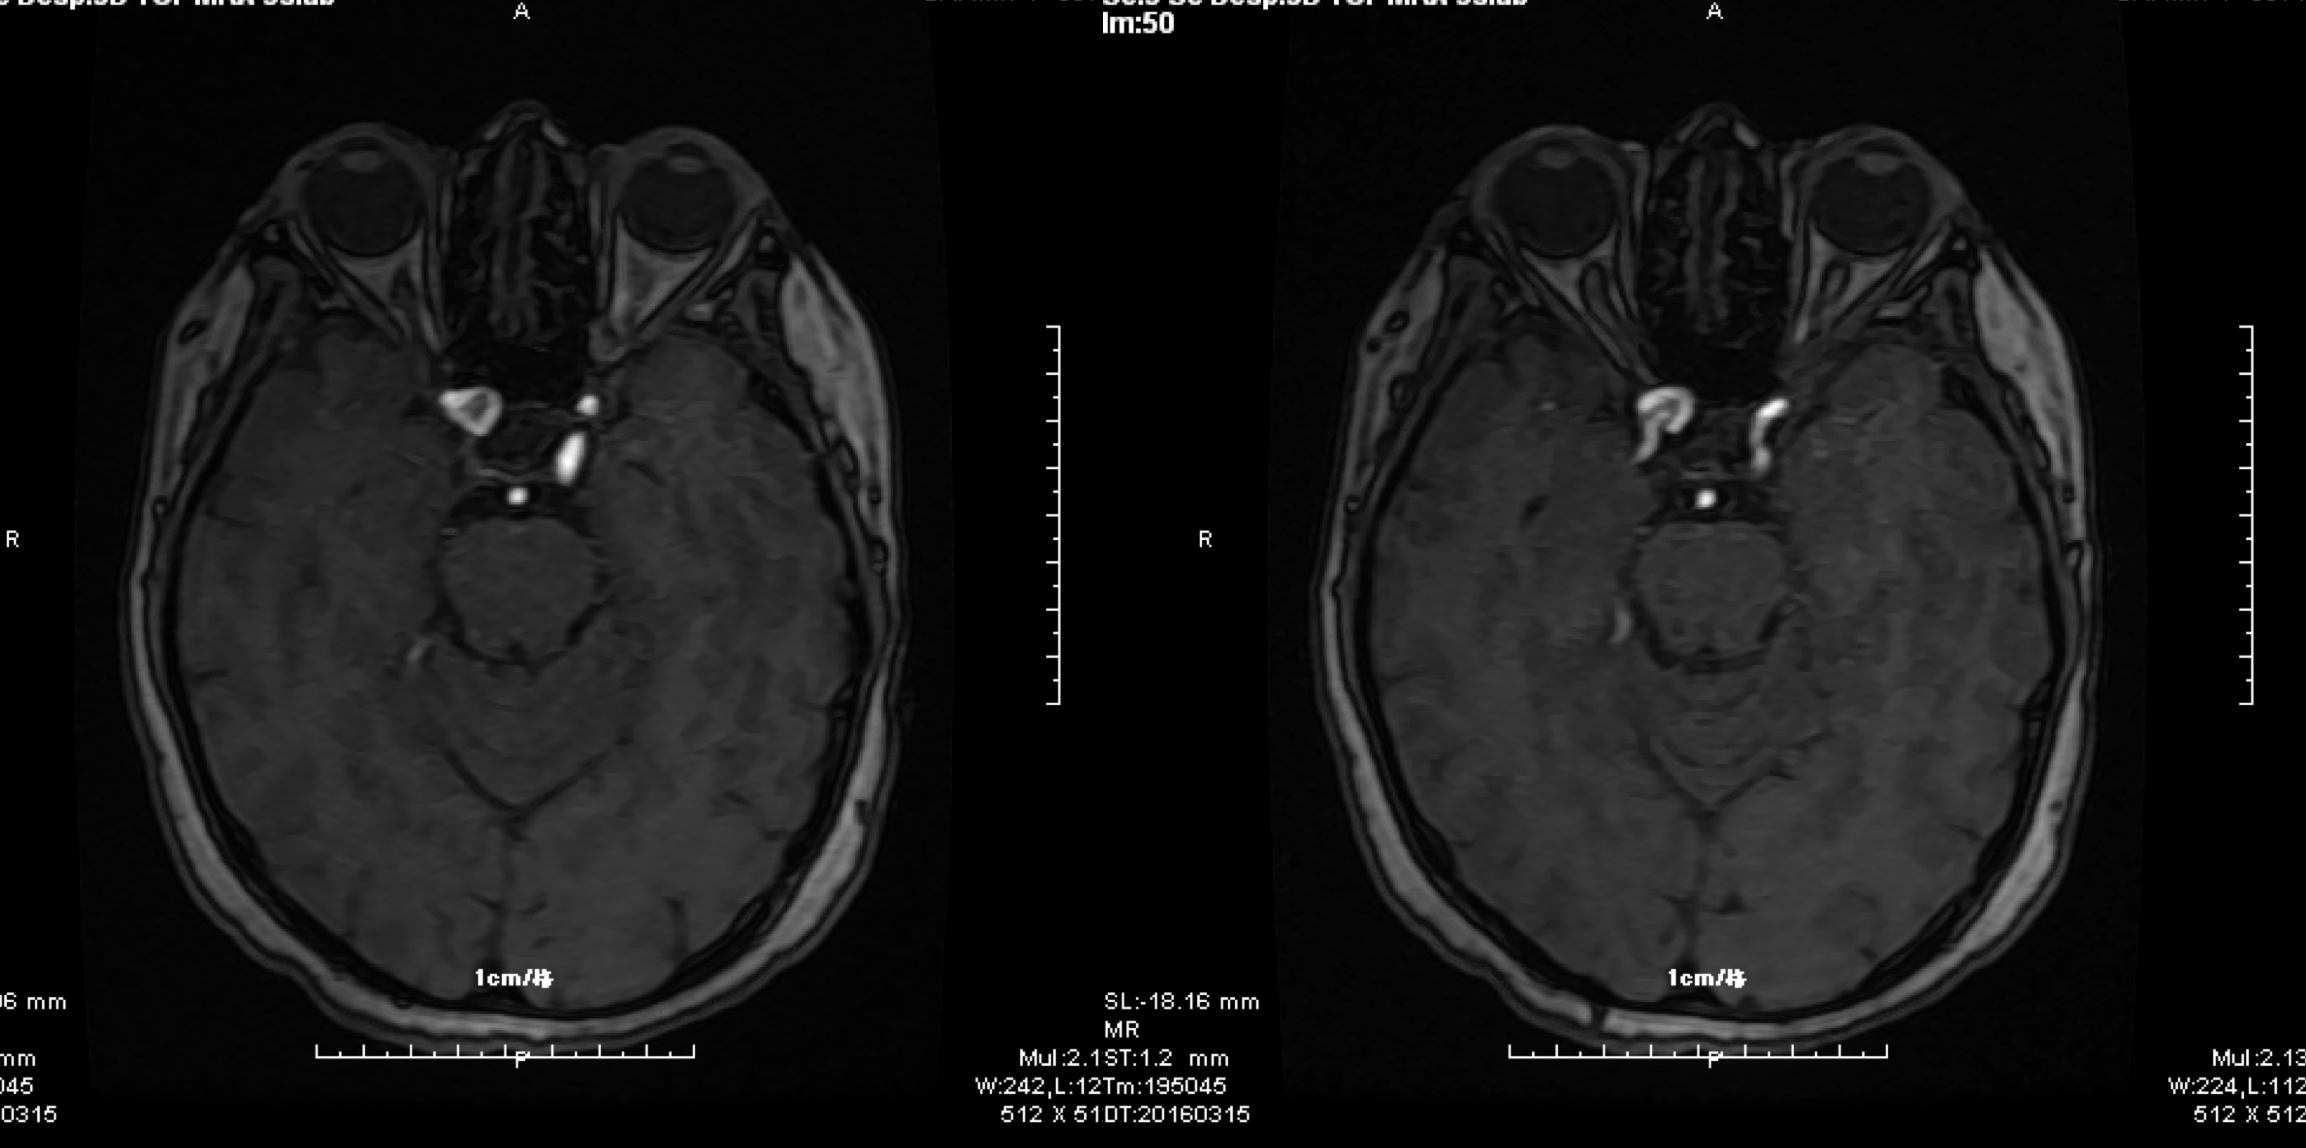

入院头颅MR:右侧眼动脉段动脉瘤.

入院头颅MRA:右侧眼动脉段动脉瘤.